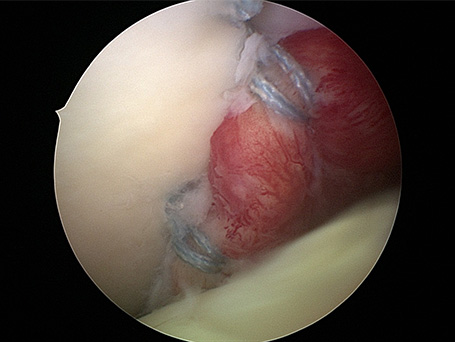

69-jähriger Patient mit linkseitiger Schulterluxationsverletzung. Bei älteren Patienten kommt es im Rahmen der Schulterverrenkungen häufiger zu Sehnenabrissen am Oberarmkopf. Trotz der Einrichtung des Gelenkes kann der Arm nicht wieder gut bewegt werden. Erst die operative, in diesem Falle rein arthroskopische Rekonstruktion der Sehnen und deren Einheilen ist eine Schultergelenksbewegung wieder gut möglich.

Junger Patient mit dorsaler Instabilität nach vorangegangenem Trauma und dorsalem knöchernem Pfannenrandabbruch. Intraoperativ bereits völlig fest verheiltes Knochenfragment. Stabilisation mit Reschspan über arthroskopisch gestützte Technik mit funktionell unauffälligem schmerzfreiem klinischen Ergebnis .